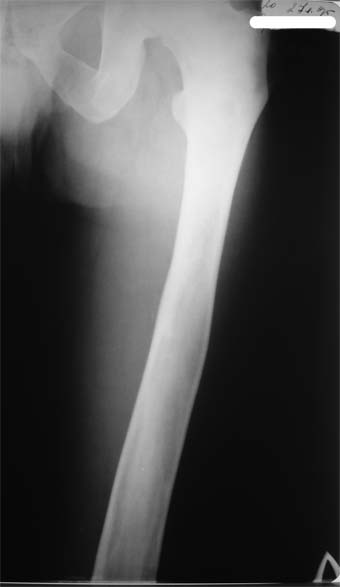

В приложении вид больного и рентгенограммы бедра 2001 год и 2005 год.

2005

У больного полиоссальноая форма фиброзной дисплазии с поражение левой бедренной и большеберцовой кости. На рентгенограммах - тотальное разрастание и остончение кортикального слоя. Имеется удлинение левой нижней конечности на 2,5-3 см за счет голени. Больному показано оперативное лечение левой большеберцовой кости.

Пациента напугали, что срочно надо оперироваться, пока не произошел патологический перелом.